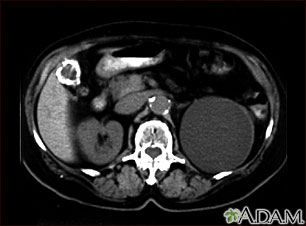

Tests used to detect gallstones or gallbladder inflammation include:

- Ultrasound, abdomen

- CT scan, abdomen